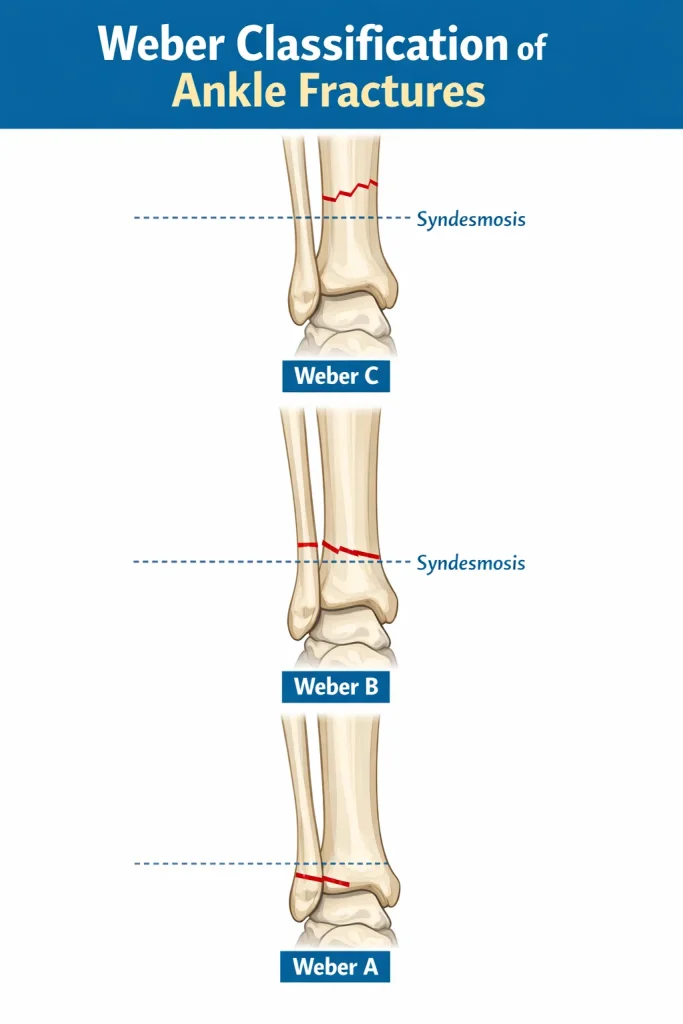

The Weber Classification of Ankle Fracture is one of the most widely used systems to categorize ankle fractures. It classifies distal fibula fractures based on their level relative to the syndesmosis – the ligament complex that connects the tibia and fibula. This simple but powerful system helps doctors determine fracture stability, the need for surgery, and expected recovery time.

The Weber classification system categorizes ankle fractures based on the location of the fibular fracture relative to the syndesmosis.

It divides fractures into three types:

- Weber A – fracture below the syndesmosis

- Weber B – fracture at the level of the syndesmosis

- Weber C – fracture above the syndesmosis

The higher the fracture, the greater the likelihood of syndesmotic injury and ankle instability.